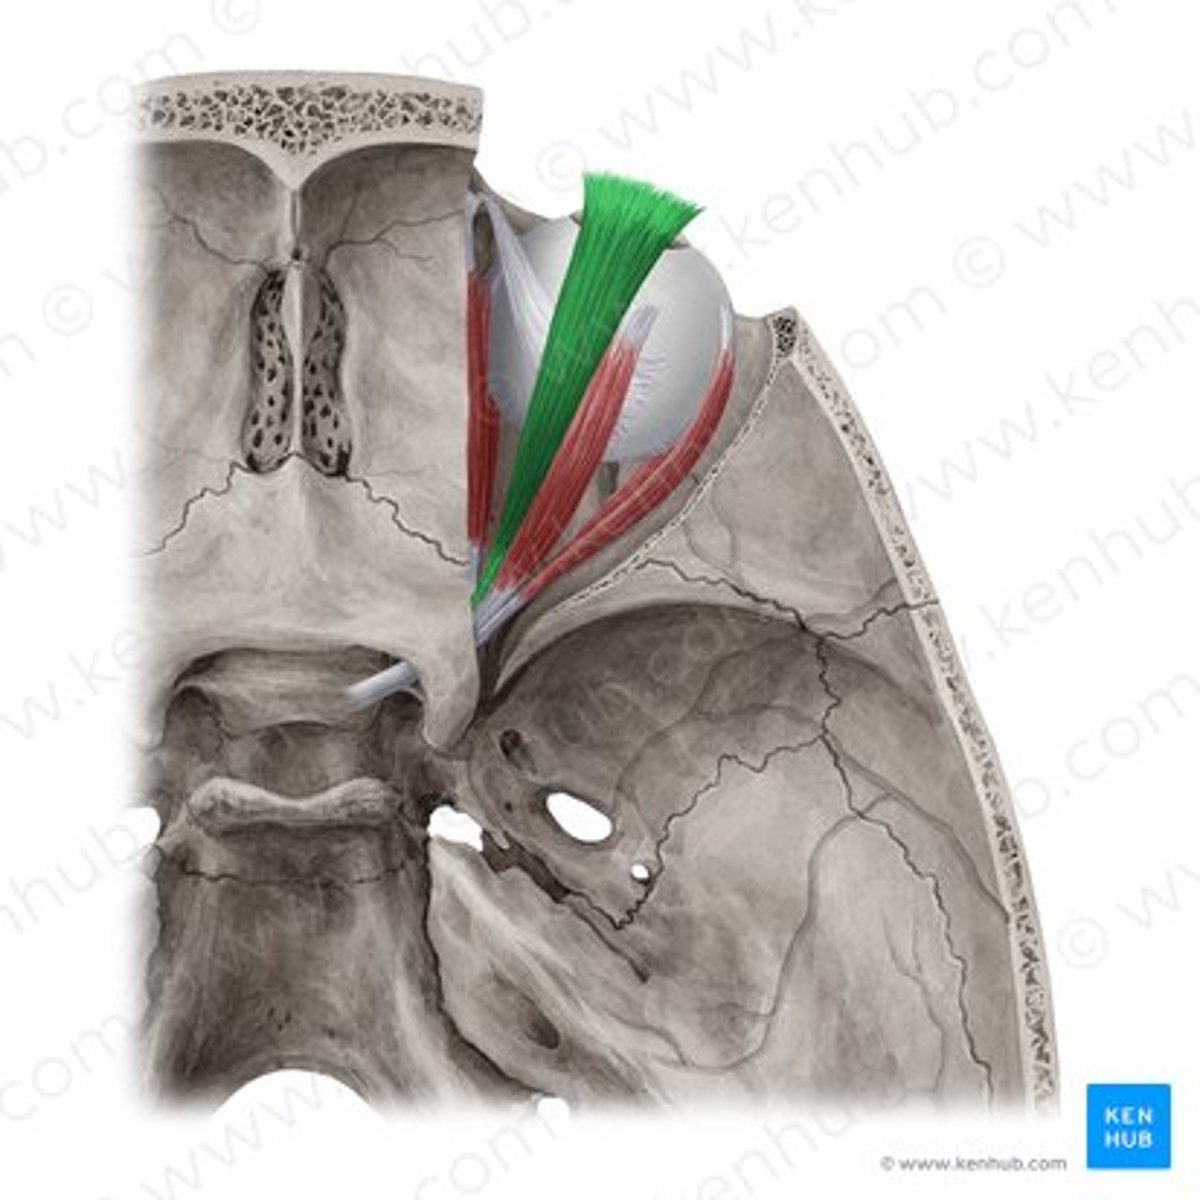

levator palpebrae superioris

superior rectus

superior oblique

superior oblique

superior rectus